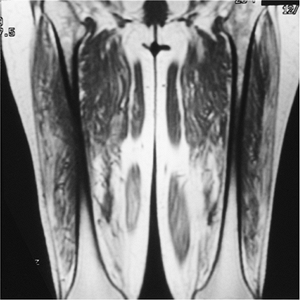

![]() |

FIGURE 13-18 Myositis. Coronal T1-weighted image of the thighs showing fatty infiltration of the muscles caused by chronic myopathy.